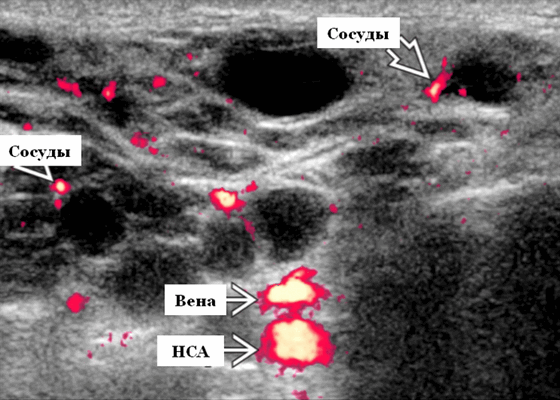

- Серошкальное УЗИ. Спектр сонографических находок от простых кист до смешанных и солидных образований. Кистозные, смешанные и солидные поражения могут возникать одновременно в околоушных железах. Кистозные поражения (кисты ДЛК). Хорошо очерченная киста, разного размера, от анэхогенной до гипоэхогенной структуры с задним акустическим усилением. Сеть тонких перегородок ± муральные узлы. Часто встречаются внутренние эхо, которые могут быть мобильными. Сотовидная внешность паренхимы околоушной железы, когда она диффузно изменена з а счет кист. Смешанные поражения (ДЛП). Границы могут быть плохо очерченными, разного размера. Структура преимущественно гипоэхогенная, железы могут быть неоднородными. Без заднего акустического усиления. Солидные поражения (околоушная лимфаденопатия). Множественные овальные / круглые, гипоэхогенные, внутрипаротидные лимфоузлы на УЗИ. Четкий корковый слой ± сохранная корневая архитектура. Сопутствующая реактивная шейная лимфаденопатия

- Цветной допплер. Кистозные поражения: от бессосудистого до умеренного сосудистого кровотока в перегородках, интрамуральных лимфоузлах и на периферии. Смешанные поражения: переменная, васкуляризация от легкой до умеренной. Солидные поражения: внутрипаротидная васкуляризация.

Серошкальное УЗИ. Одиночные или множественные гипоэхогенные образования в известном распределении внутрипаротидных лимфоузлов. Хорошо выраженный или слабо окаймленный (экстранодальное распространение). Экстранодальное распространение. Обратите внимание на местную инвазию интрапаротидной наружной сонной артерии (ВСА), ретромандибулярной вены или экстрапаротидных мягких тканей. Аномальная внутренняя архитектура ± эхогенные ворота. Однородный или неоднородный вид с внутренними кистозными участками в некротических узлах ± метастазы в шейные лимфатические узлы

Энергетический допплер. Внутриочаговая васкуляризация. Хаотический / дезорганизованный или преимущественно периферический кровоток